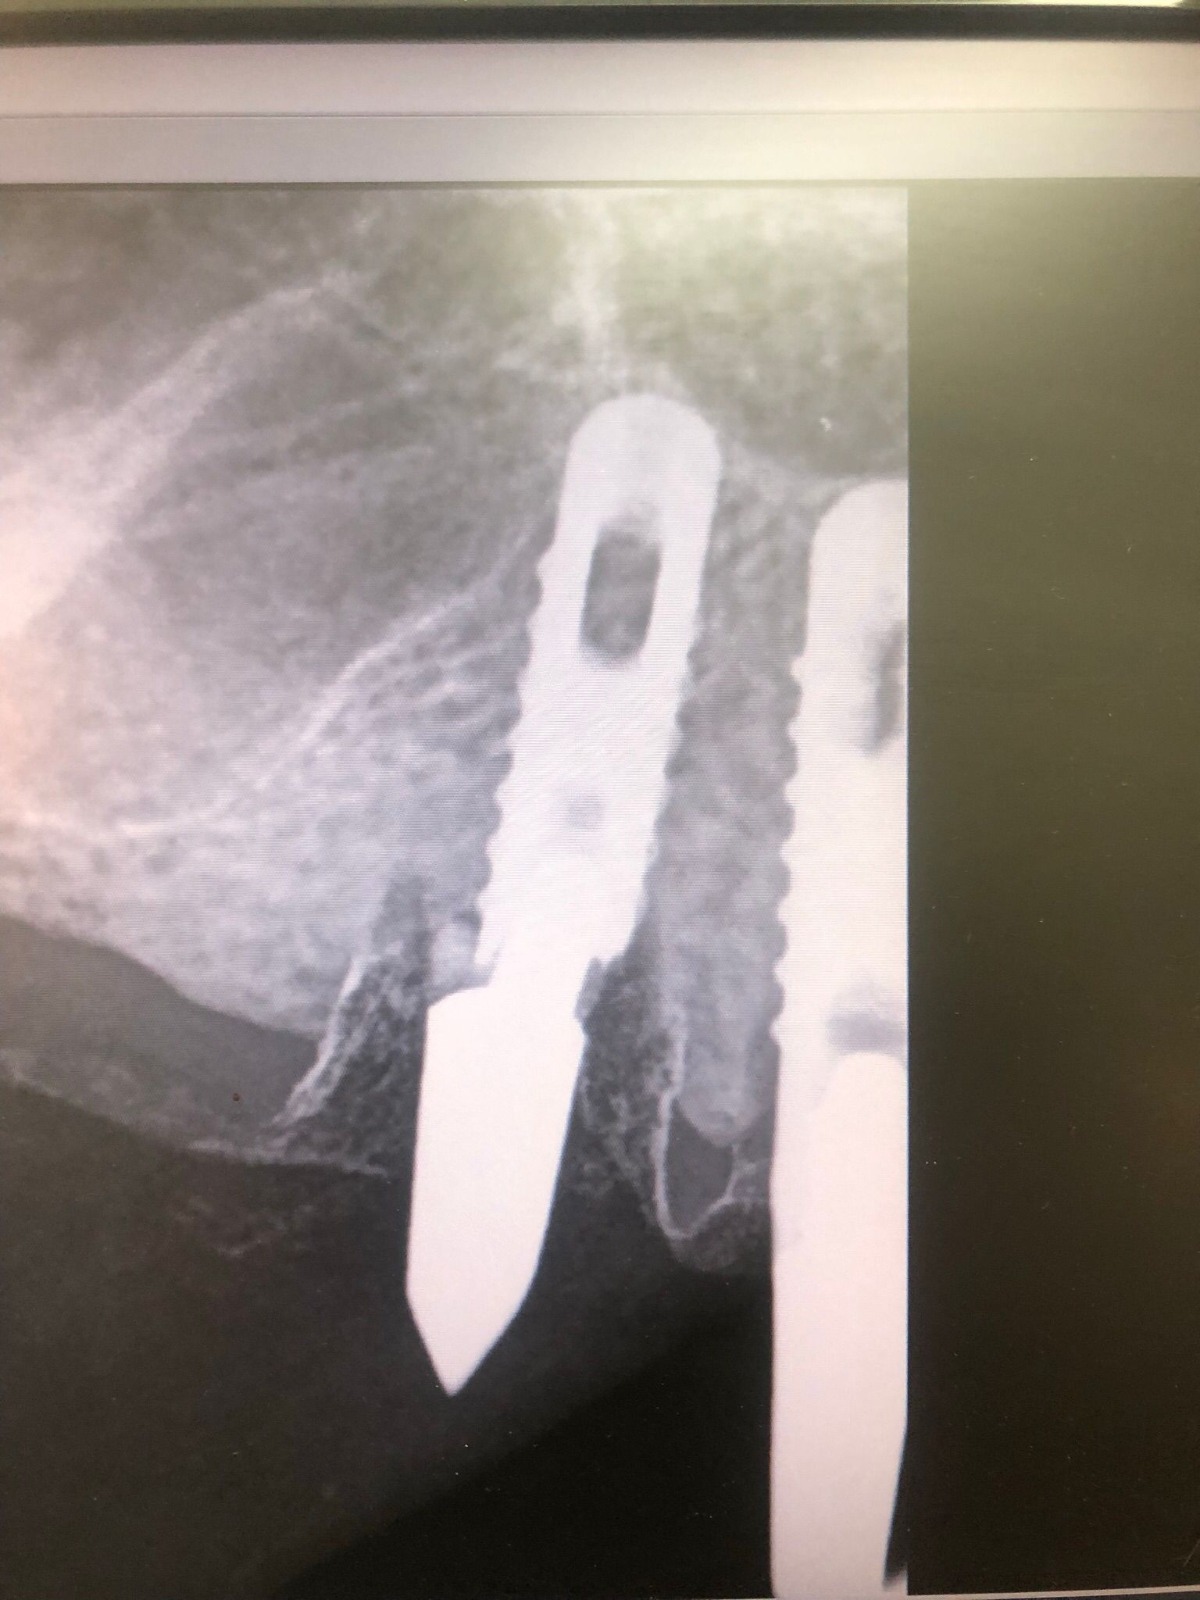

Actualmente vuelve el paciente de nuevo con la misma prótesis. Había roto dos de los tres pilares en concreto los más distales. El primero de los dos había roto la rosca del aditamento dentro del implante como ocurre habitualmente. Pero el ultimo pilar había roto directamente la cabeza del implante tal como se ve en la radiografía y lo que quedaba era un cilindro de titanio macizo perfectamente integrado en el maxilar, sin posibilidad de enroscar nada. Le explicamos al paciente que habría que quitar y poner un implante en el mismo acto. El paciente dijo que no, así que decimos que no se haría cirugía. Buscamos solución alternativa: hacemos un un agujero en el centro del macizo cilíndrico del implante roto y pasamos sucesivamente el set de machos roscantes. Utilizamos una fresa cañón de 1 mm que poco a poco se va introduciendo hasta 8mm con un poco de vagación, que hace que sea un poco mas de 1mm de diámetro. Posteriormente pasamos el conjunto de machos roscantes de métrica 2mm para poder usar un aditamento experimental, que era un palo de rosca de diámetro 2 mm unido a un cuerpo metálico en forma de sombrero napoleónico fabricado en cromo/cobalto, prototipos primitivos de la sistemática ASATIM y que tienen la característica de tener gran resistencia a la fractura. Nos llevó un tiempo largo el tallado de dichos aditamentos, tal como se puede observar en las imágenes, y tras cicatrizar la encía se le hizo una prótesis estándar. Esperemos que no lo rompa más veces.